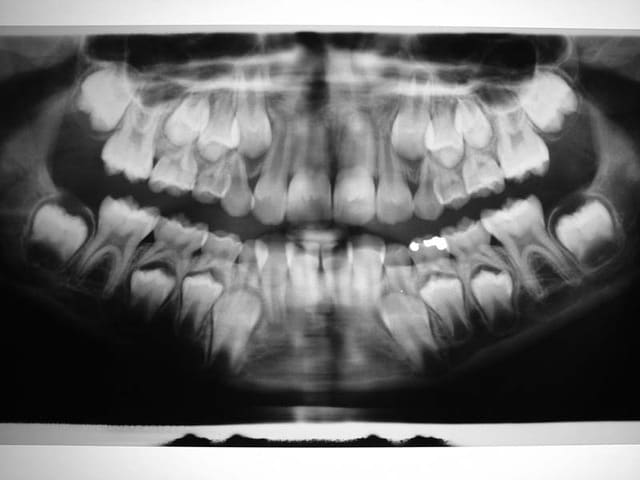

C’est un cas que j’ai traité en deux temps, interception, période d’interruption, fin de TTT.

ce n’est pas un cas trop difficile, aussi j’ai assez peu de photos

Avant TTT.

à suivre Bjc.

c'est le mm. patiente

la coloration des dents est assez remarquable

P.S.: j'avais à l'époque un Fuji mono-objectif

les photos de la contention ont été prises avec un Canon 1000 objectif Macro

les couleurs ne sont pas tout à fait les mm.

mais les dents ont gardé la mm. forme et les taches sont reconnaissables